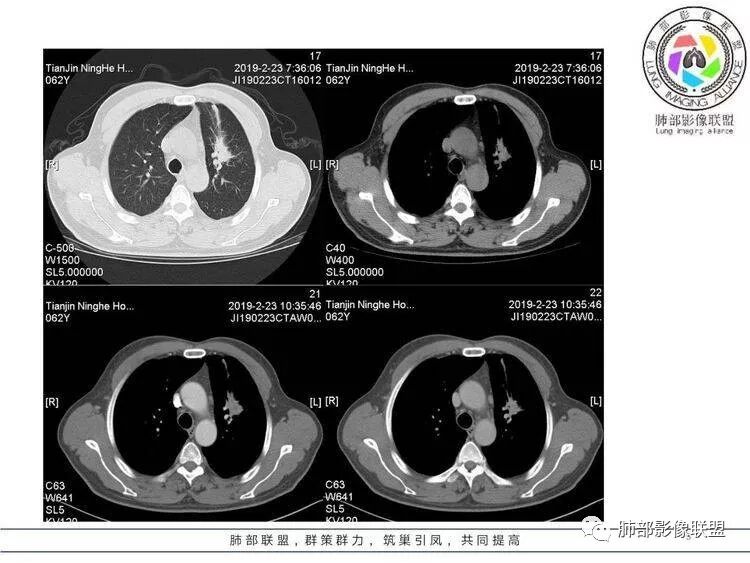

王秀仙:左肺上叶肿块,边缘平直收缩,周围可见长索条,轻度强化,密度不均可见低密度坏死,考虑结核。鉴别腺癌。Yiren  Sishui(厶水伊人):晨读:左肺上叶肿块,近胸膜侧光滑,提示符合淋巴回流病变,周围条索,符合肉芽肿性病变,环形强化,中心坏死,考虑结核可能luys:左肺上叶病变,沿支气管分布,边缘平直收缩,周围见长索条,轻度强化,伴边界可见低密度坏死灶。考虑特殊感染。灶内支气管中断,临床以咯血就诊,鉴别肿瘤。博麟:左上胸廓稍缩小,长条索病灶,冠状位似见支气管截断,坏死边界似乎欠清,猜个纤维条索基础上合并瘢痕癌红日东升:晨读:左上叶结块,前缘有粗大索条向前延伸,邻近前联合线明显左移,提示收缩明显。结块边缘平直、收缩;增强结块及索条明显强化,内血管走行自然,坏死灶周围似见三层结构;考虑炎性病变。wonderful:肿块实性边缘光滑  考虑良性病变 合并咯血 。结核或曲霉玫:左肺上叶不规则形软组织密度肿块影,边界清晰,期内密度不均匀,可见坏死,病灶向前呈条索状延伸,矢状位病灶形态欠规整,似有血管中断,考虑恶性病变可能,待除外结核?张帅:左肺上叶病变,病变周围平直,长毛刺,病灶内可见低密度区及支气管征,矢状位提示前段阻塞,病灶内气管不规则扩张,病灶周围有卫星灶,考虑良性病变:结核?我心飞翔:病灶边缘平直,中央可见坏死,周围磨玻璃边界欠清,考虑炎性病变张延军:左肺上叶尖后段肿块,边缘以平直为主,局部膨隆,内见片状坏死区,边界欠清,相应尖后段支气管闭塞,考虑占位并不张,腺癌?建议抗炎治疗后复查丽:左肺上叶病变,边缘平直,并可见长索条,增强后密度不均,可见坏死,首先考虑结核,但重建后支气管走形欠连续,似有截断,恶性待排毛勤香:左肺上叶病灶,边缘平直为主,周围索片影,增强强化不均匀,内有坏死,重建支气管走行欠规则,似有截断,老年男性,需排除恶性(鳞癌?)并阻塞性肺炎可能王萍:左肺上叶团片,大部分边缘平直、凹陷,周围见少许条片模糊影,增强内见坏死区,余区域较均质,其内支气管部分通畅,部分变窄。咯血病史,无发热,考虑肉芽肿性炎可能性大,结核或放线菌等,肿瘤待排THINKER:左上叶,占位,围绕尖后段支气管,U型凹丶平直,长索条,有轻强化及低密度,考虑良性的,首选OP,老年不发热丶咯血,鉴鳞癌、TB飞鹰行动:左肺病灶,有明显的收缩表现,增强后病灶内部可见低密度无强化区,病灶内支气管轻度扩张呈串珠状改变,支持炎性病变,结核可能性大。杨泽锋:支持炎性病变伴小脓腔形成,但不支持结核,因为病灶内可以可见血管影THINKER:问一下各位老师:这个给的强化,是肺动末期丶主动脉未期`延迟期?大雄:老年男性,左肺上叶前段条片状实变影伴周围长条索,境界清晰,边缘部分锐利光滑、部分毛糙,增强可见中央局部坏死,周围无强化区轻中度均匀强化,无钙化,无明显卫星灶,无胸膜明显牵拉凹陷。病灶整体收缩力有,张力不明显,肿瘤概率小。临床无明显急性感染症状,倾向于慢性增生性炎症,累及段支气管,引起了咯血。结核多见,但慢性结核肉芽肿一般强化没这么明显。OP不除外。老年男性如果有长期吸烟史,鳞癌不能完全排除,鳞癌的坏死强化都符合,鳞癌收缩力也不强,形态更是变化无常左手:老年男性,咯血,左肺上叶长条样结节,边缘见牵拉影,支气管堵塞,病灶内见坏死,坏死边缘偏清,考虑鳞癌,鉴别结核宇宙星空:支持恶性。鳞癌可能性大。支气管截断及空泡征

Shelia:考虑机化性肺炎伴小脓肿形成?炎性肌纤维母细胞瘤?鉴别癌食客:左肺上叶病灶,边缘平直,周围条片影,增强内见坏死区,内支气管部分通畅,咯血病史,无发热,考虑结核,肿瘤不除外。管洪林:左肺上叶尖后段病变,整体边缘平直,部分稍收缩,临近长索条影,胸膜缘可见轻度牵拉,增强后整体强化明显,其内可见低密度类圆形坏死区,边界清,首先考虑op并小脓肿形成,但部分层面显示小支气管受阻,是否层面原因?管洪林:若是支气管阻塞,鳞癌作为鉴别雪上一枝蒿(陈显静):他这个动脉期是不是不是很明显啊,觉得跟静脉期差不多,强化值也不好分辨?徐超:左肺上叶实变,边缘平直,周围无磨玻璃及卫星灶,病灶内坏死,强化后边界清楚,无壁结节,余病灶轻中度均匀强化(对比肌肉),增强后血管显影清楚自然,未见破坏边缘毛糙,血管旁条形无强化区(粘液?)整体符合炎性特点,炎性假瘤或op可能,伴小脓肿;结核放后面待排(结核病灶内血管完好,边缘清楚,且强化近中度,不是很合理,肉芽肿到也可以)。红日东升:平扫和强化窗宽窗位不一样良孑:左上实变,有平直及长毛刺,其内支气管牵拉性扩张,提示收缩力较强,无卫星灶,强化不支持TB,均匀强化,无分叶不支持鳞癌,影像上提示慢性进程,考虑OP并脓肿,鉴别炎肌母。

1.外观呈三角形,尤其是锐三角形的病灶,一般是最不支持肿瘤的。

2.小病灶影像上观察到液化坏死一般不支持肿瘤。

3.腔内壁太规则一般不支持肿瘤。

4.炎性分泌物可以形成一定程度堵塞,但很少截断支气管。

5.结核可以强化不显著,但病灶不靠边,没有卫星灶,似乎支持点不多。